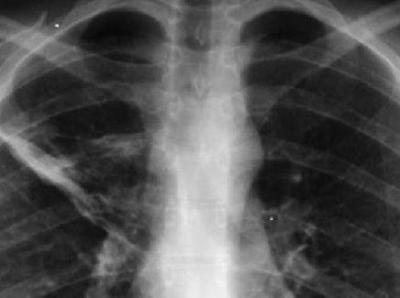

यानंतर डॉक्टरांनी महिलेच्या छातीचा एक्स-रे काढला. त्यात तिच्या फुफ्फुसाच्या उजव्या बाजूला प्लास्टिकसारखी वस्तू आढळून आली. ही वस्तू गोल आकाराची होती.